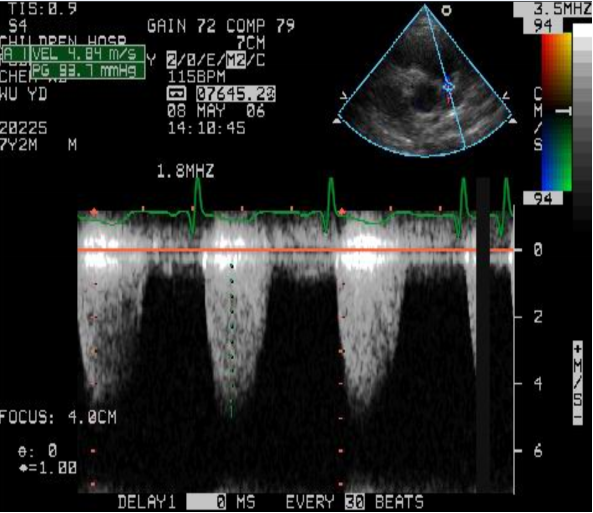

右室流出道狭窄

连续波多普勒测量右室流出道压差